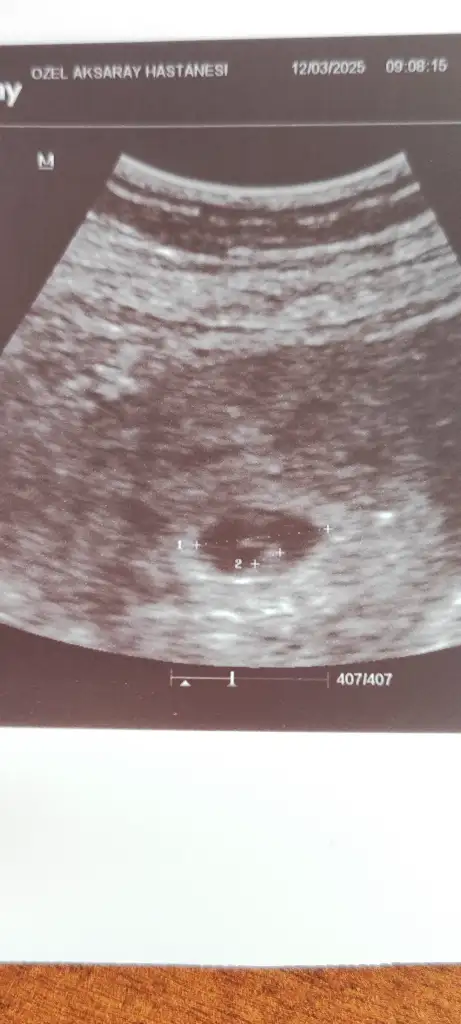

Benim icinde tahminde bulunabilir misiniz 11+4 haftalıkErkek bu bencedoktor söylemedi mi? Kaç haftalık burda

Bu kız bebek benceBenim icinde tahminde bulunabilir misiniz 11+4 haftalık

Yukarida benim attigimda var bakabilir misinBu kız bebek bence

Merhaba onun nub teorisine göre çıkıntısı paralel durduğu için kız diye tahmin ettim,sizin görüntü karından alındıysa ramzi teorisine göre erkek duruyor6 haftalik tahminde bulu